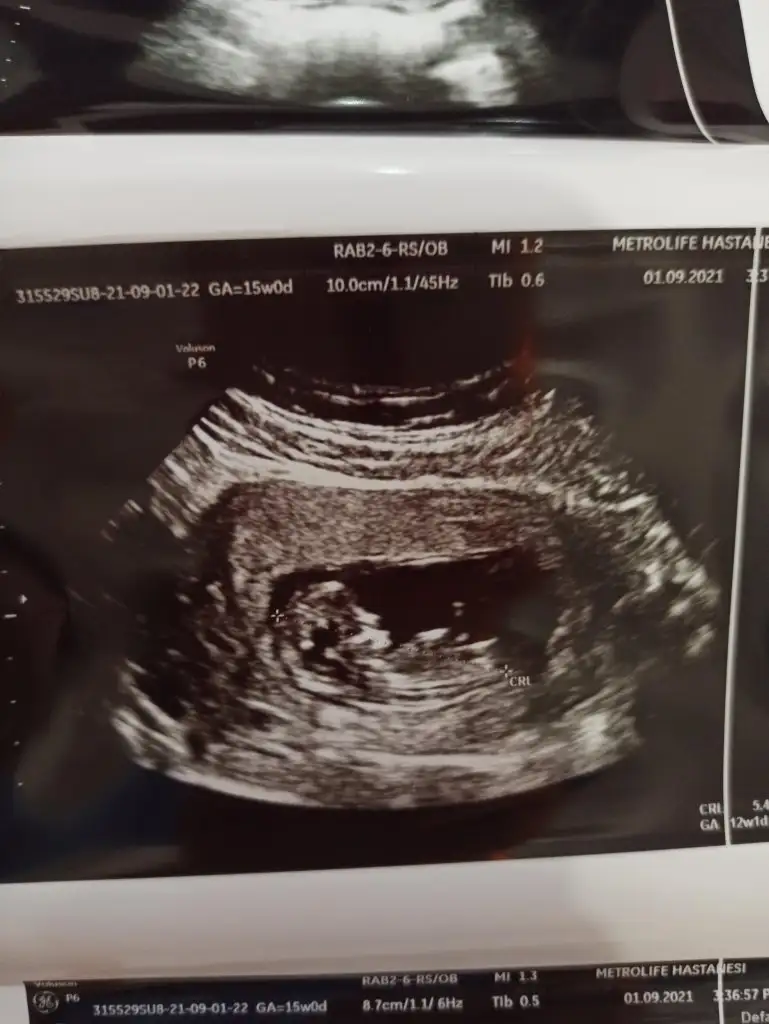

Emin olamadim kız gibi sankiBizde bugün kontrolden çıktık 12+3 haftalığız ,doktor cinsiyet için emin olamadı resimlerden siz yorum yapabilirmisinizIkra meyra

Erkek sanki sizin usgler net değilBu ultrason resmini gore bellimi acaba nub bi bakarmisiniz ikra meyra

Doktorda bir kız bi erkek dedi bakalım 3 hafta sonra kontrol var gösterir ozaman inşEmin olamadim kız gibi sanki

Kız gibiKizlar bu da benim yavrum 12+3 sizce nedir çok merak ediyorumEki Görüntüle 2910088